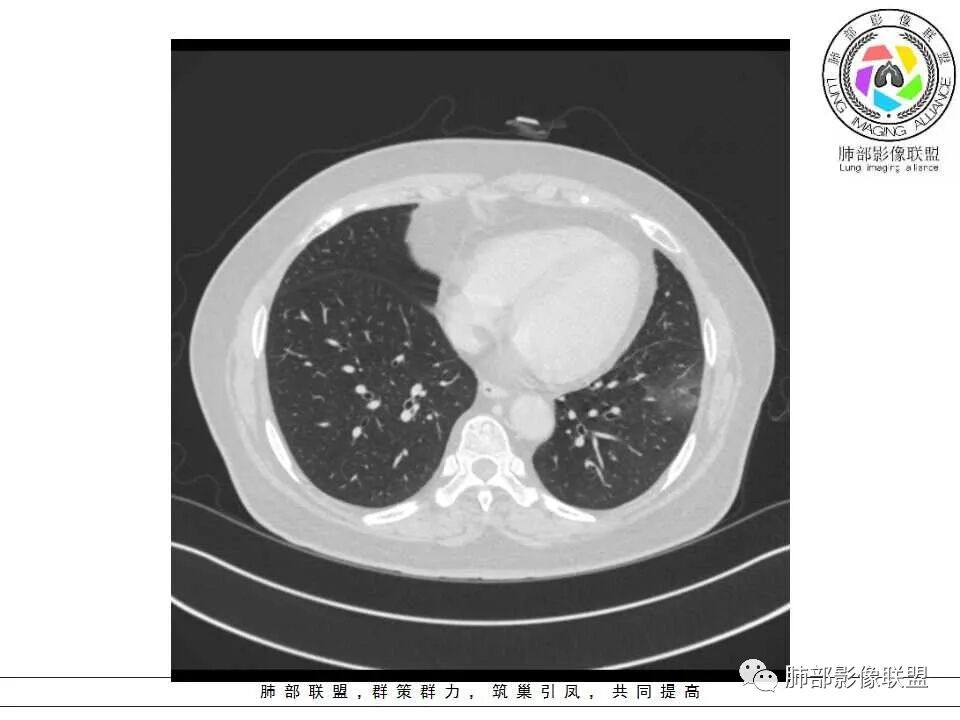

患者,女,65岁,2月余前受凉感冒后开始出现咳嗽,咳白痰,初发热2天,体温38℃左右,后降至正常,咳嗽无好转。近2日咳嗽加重,痰量增多,为黄白痰,无发热,无乏力、盗汗,无胸痛、胸闷,无头晕、头痛,无恶心、呕吐。PET-CT检查提示炎性病灶与恶性结节鉴别困难。

病灶分两部分

周围大片GGO

中央囊实性病变

南边:

病史没提咳血,周围出血灶似乎不太好说

部分边界偏清

囊腔有张力,外形有分叶,壁厚薄不均,有间隔,有强化

哪些病变可能?

1、癌

2、炎性:曲霉菌?

3、良性:囊腺瘤样畸形合并感染

1、左肺下叶外基底段不规则囊腔样病灶,囊腔内有条形影及血管穿行。

2、囊壁薄厚不均匀,稍显僵硬,有壁结节(对应边缘分叶等)、结节强化明显。

以上两条几乎将肺囊肿彻底排除在外,且高度怀疑新生物!

3、灶周环以大范围磨玻璃影,非常均匀,没有重力分布趋势,分叶状,边界隐约可变。

4、冠状位部分层面可见支气管在囊腔边缘截断。